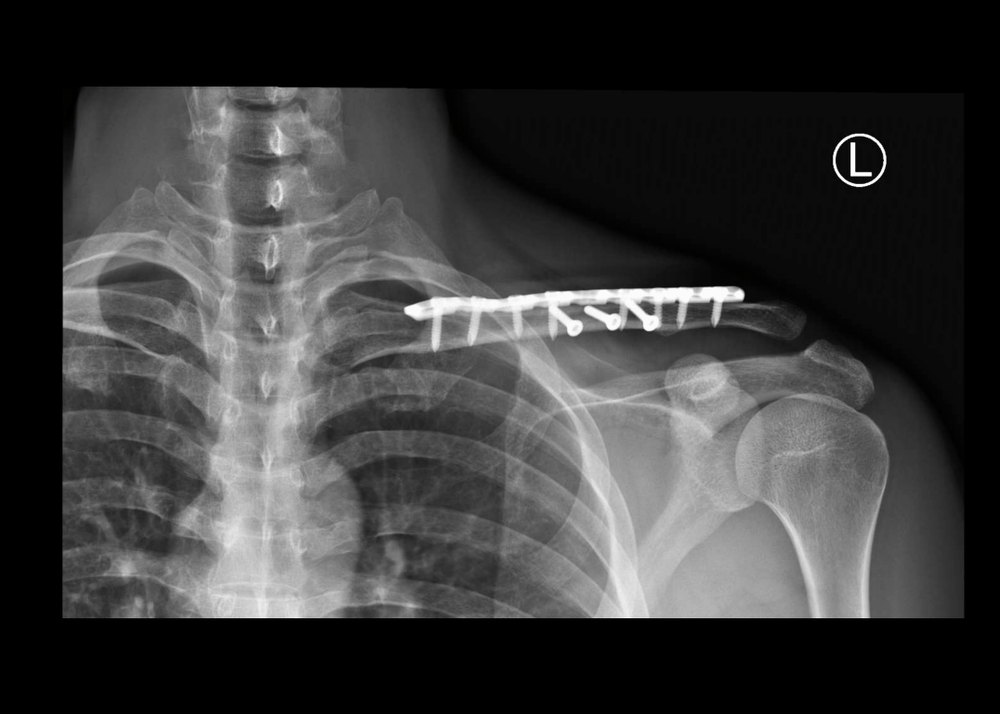

fractura grave en el brazo cerca del hombro

Para el reemplazo total del hombro, el extremo redondo del hueso del brazo se reemplazará con una caña o vástago artificial que tiene una cabeza de metal redondeada. La parte de la cavidad (glenoide) del omóplato se reemplazará con una cubierta plástica y lisa (recubrimiento) que se sostendrá en el lugar con un cemento especial. Si sólo 1 de estos 2 huesos necesita ser reemplazado, la cirugía se denomina artroplastia parcial del hombro o hemiartroplastia.